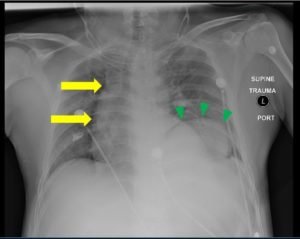

Although uncommon, traumatic diaphragmatic rupture (TDR) from blunt force injury is difficult to diagnose and can lead to serious complications if left untreated. Associated symptoms are often non-specific, which can make detection of the injury difficult. Here we present a case report of a patient who suffered a left-sided TDR after blunt trauma. Upon arrival at the emergency department, the patient denied pain but had tenderness to palpation over the epigastrium. A chest X-ray showed an elevated diaphragm on the left with mediastinal shift to the right, and a diagnosis of TDR with stomach herniation was confirmed by computed tomography (CT). The patient was admitted to surgery for reduction and repair and later discharged in good condition. This case report highlights the importance of suspecting TDR in high energy injury mechanisms presenting to the emergency department.